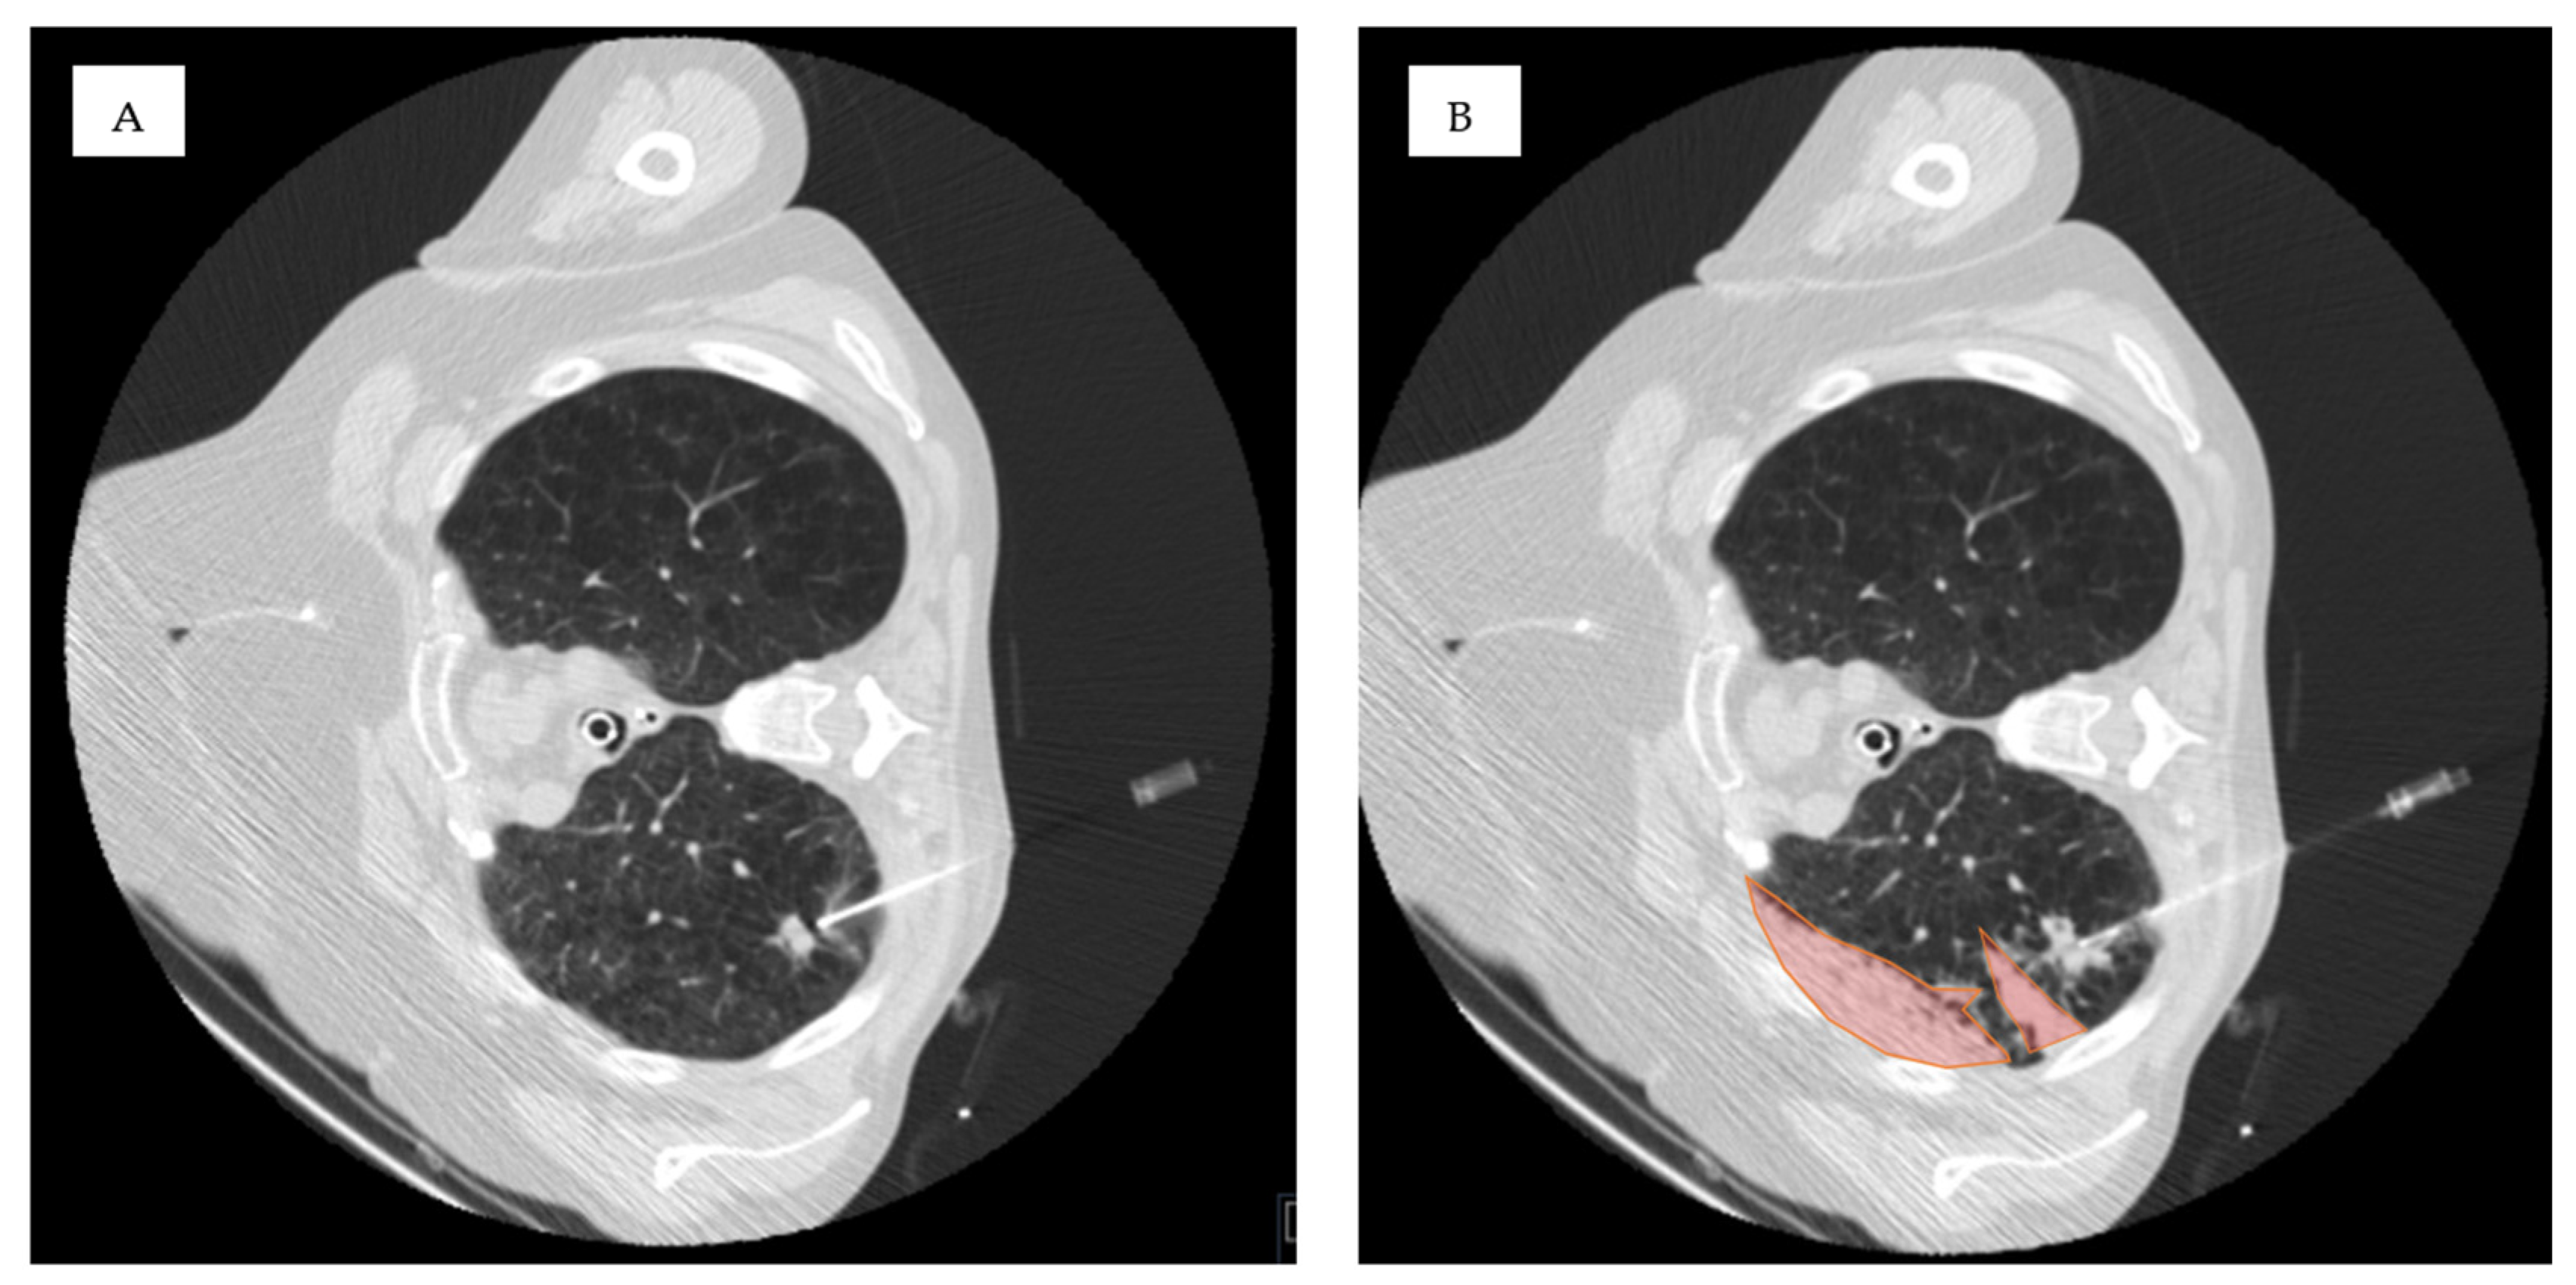

| Ground-glass in the access route | 46 | 40% | 26 | 31% | 20 | 67% | 0.001 * |